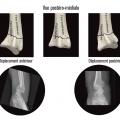

Au niveau métaphysaire le déplacement peut être postérieur ou antérieur (fig. 6). En ce qui concerne le déplacement postérieur, il est important de se souvenir que la surface articulaire regarde vers l’avant. En d’autres termes, dès que cela n’est plus le cas, même si la surface articulaire n’est pas orientée vers l’arrière, il s’agit d’un déplacement postérieur. Classiquement, le déplacement postérieur est lié à un mécanisme dit en compression-­extension, c’est-à-dire une chute sur la main, le poignet étant en extension (fig. 7). Le déplacement est dit antérieur s’il y a une exagération de l’orientation antérieure de l’épiphyse radiale. Ce déplacement est classiquement lié à un mécanisme dit en compression-flexion, c’est-à-dire une chute sur la main, le poignet étant en flexion (fig. 7). La plupart du temps, ce déplacement postérieur ou antérieur s’accompagne également d’un déplacement externe, avec un tassement au niveau de la corticale latérale (fig. 8). Outre le déplacement antérieur, postérieur ou latéral, il est très important d’analyser au niveau du foyer de fracture métaphysaire l’importance de la comminution qui peut être uniquement postérieure, ou antérieure, ou circonférentielle, ce qui conditionne la stabilité de la fracture et oriente vers le type d’ostéosynthèse à réaliser.